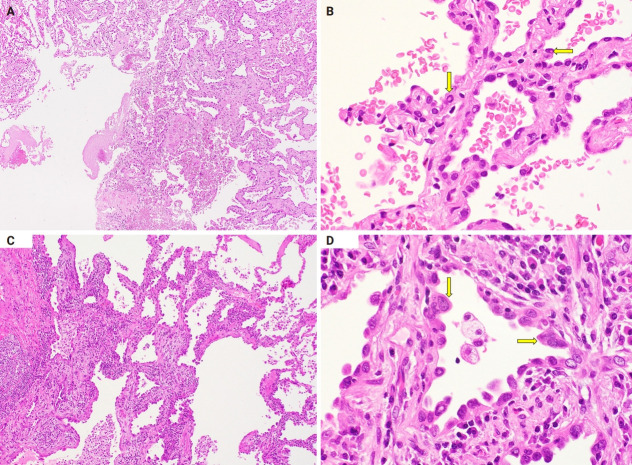

Atypical adenomatous hyperplasia (AAH) and adenocarcinoma in situ (AIS) are generally treated as different lesions, depending on the differences in lesion size and histological findings. However, these differences are not absolute; thus, AAH and AIS are often difficult to distinguish. Moreover, whether AAH and AIS can be regarded as different lesions remains unknown because cytological specimens, especially those of AAH, are rare. In this study, we examined these uncommon cytological specimens and compared the cytological findings between AAH and AIS. We observed many common cytological features with no obvious differences between AAH and AIS. These findings suggest that these two distinct lesions can be grouped into a single category. Therefore, we propose creating a new cytological category.